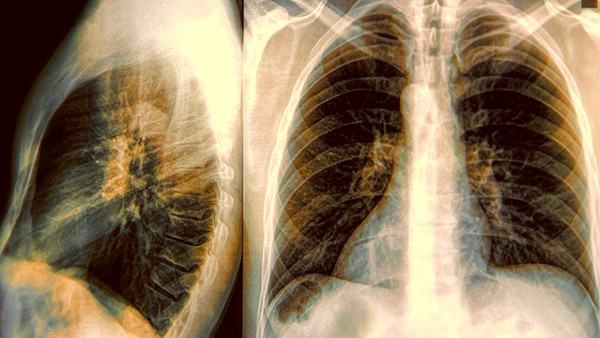

首先,纵膈气肿是指气体在胸腔内沿纵膈蔓延,导致纵膈间隙增宽,通常是由于食管、胃口、肺或支气管破裂而引起。相比之下,气胸是指气体积聚在胸腔内,通常是由于肺泡破裂导致空气进入胸腔所致。

其次,在临床上,纵膈气肿和气胸的症状和体征略有不同。纵膈气肿引起的症状可以包括胸痛、声带痉挛、吞咽困难和喉头痛等,而气胸一般表现为突发性胸痛、呼吸困难和咳嗽等症状。此外,在体格检查中,纵膈气肿患者可能出现颈部可触及的皮下气体感,哮鸣音和胸骨下方气动脉搏动的减弱。而气胸患者常常表现出肺部呼吸音减弱或消失、叩诊时呈现出移动性浊音等体征。

最后,纵膈气肿和气胸的主要病因也略有不同。纵膈气肿通常是由于外伤、手术、自发性食管破裂或器械介入引起,而气胸主要是由于肺部损伤或肺组织疾病导致气体进入胸腔。其中,自发性气胸可能与肺气肿、支气管哮喘等肺部疾病有关。

总体而言,纵膈气肿和气胸都是由胸腔内的气体异常积聚引起的呼吸系统疾病。纵膈气肿主要表现为纵膈间隙增宽、胸痛及相应的体征,而气胸则表现为胸腔内气体积聚、突发性胸痛和肺部相关体征。在临床上,医生需要仔细区分这两种疾病,并根据病因和病情合理选择治疗方法。